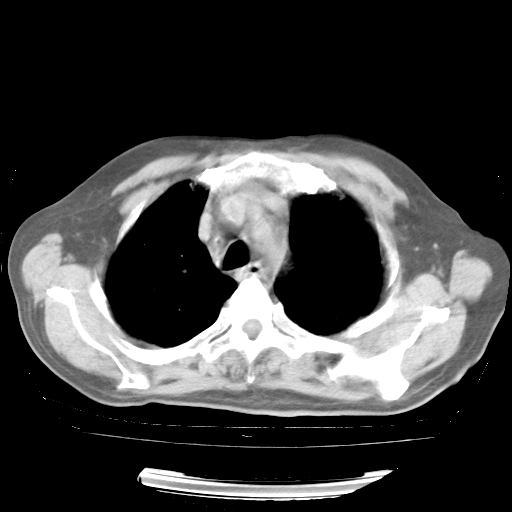

4月28日肺部CT——再次出现类似去年5月9日——透光度降低,“间质性”改变。